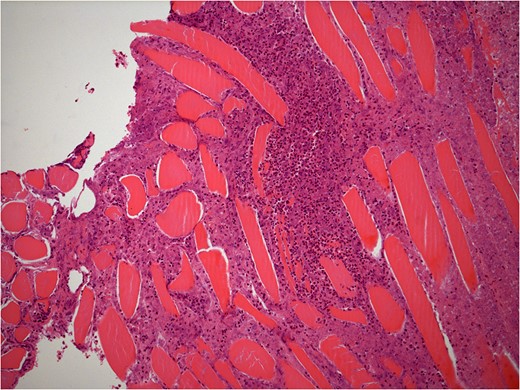

He underwent surgery to explore the tendon where an irregular, cystic, fibrofatty lesion was identified within the tendon (Figs 3–5). This was successfully resected and sent for histology which showed a florid granulomatous and histiocytic response to the suture material, in keeping with a suture granuloma (Figs 6 and 7). There was histological evidence of the abscess extending into the muscle (Fig. 8).

40× histology slide showing foreign body giant cell reaction to suture material.